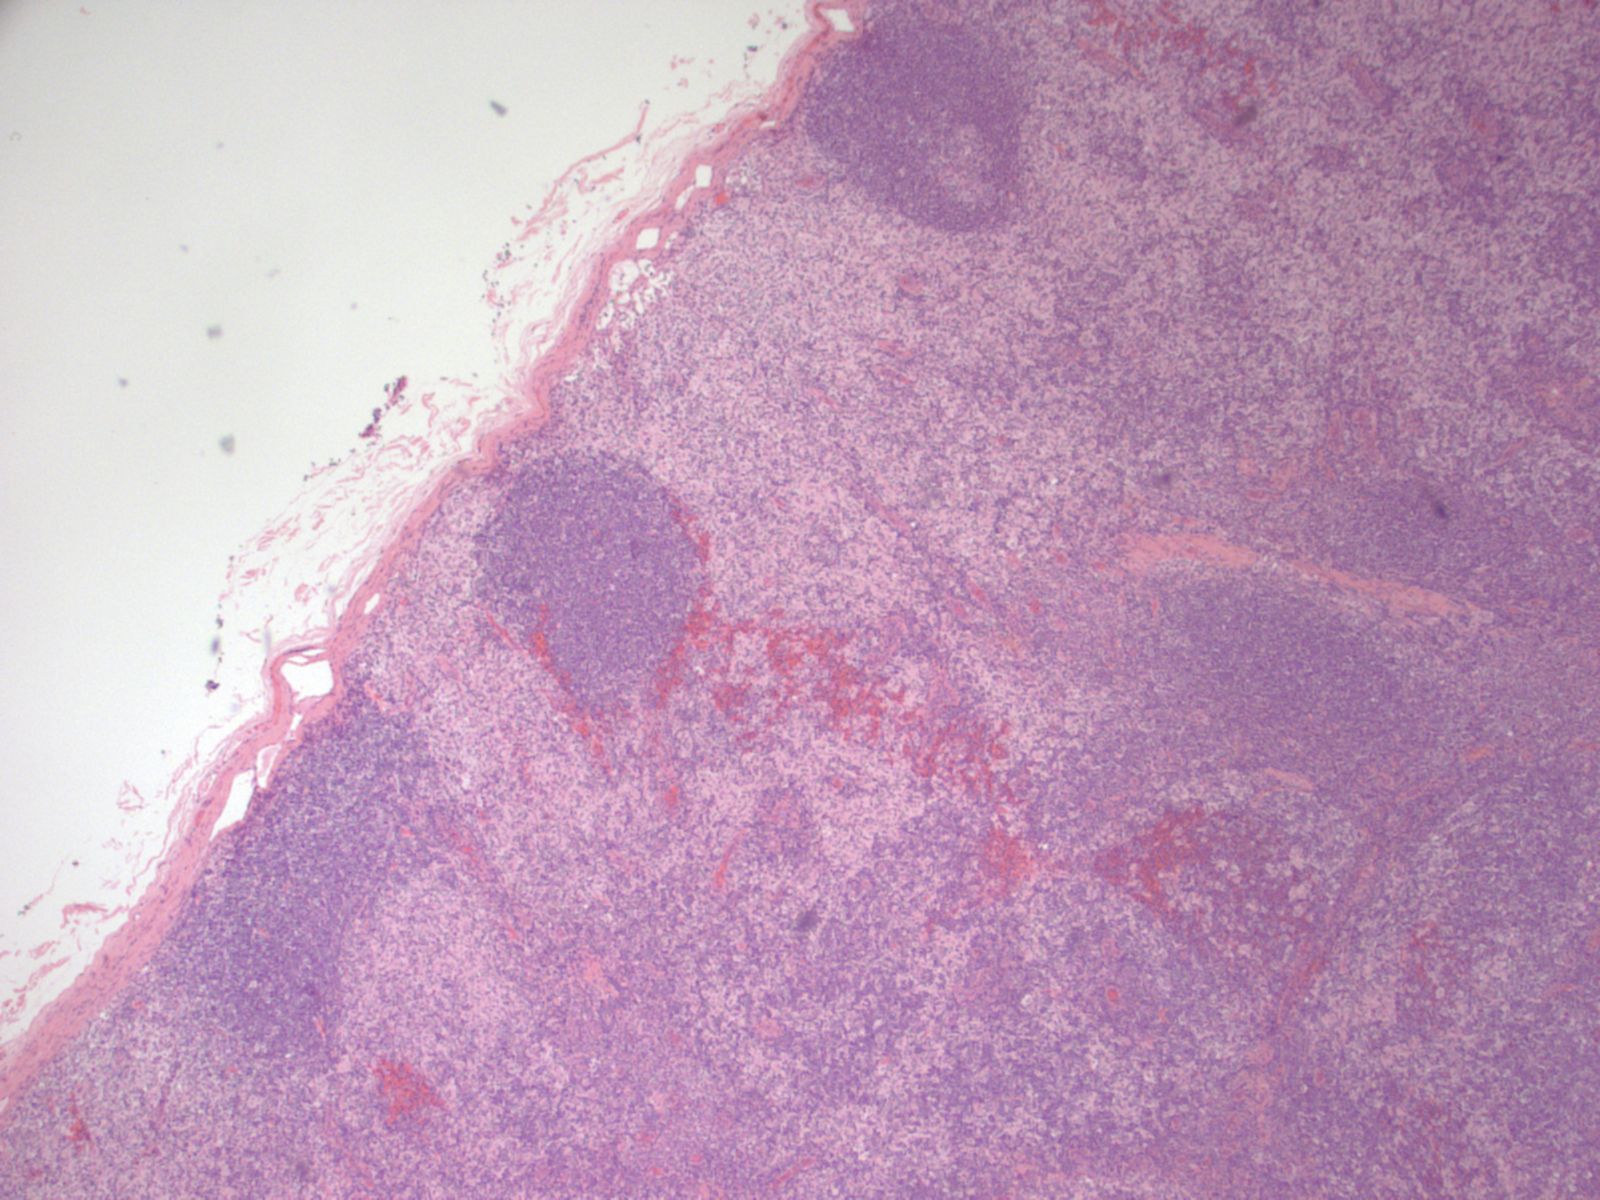

Microscopic (histologic) description

- There is always preserved nodal architecture with intact capsule

- Follicular hyperplasia may be present but it is usually minimal

- Spectrum of changes from mild to severe, characterized by paracortical expansion with pale, irregularly shaped areas containing numerous pale staining histiocytes, interdigitating dendritic cells, Langerhans cells and occasional immunoblasts

- Predominance of interdigitating dendritic cells over Langerhans cells, which are indistinguishable on morphology alone

- Both cell types show ill defined cell borders with fine irregular reniform nuclear contours and occasional nuclear grooves

- Paracortical or sinusoidal histiocytes and macrophages often contain cytoplasmic melanin pigment but they also can contain hemosiderin or lipid

- Medullary plasmacytosis is variable

- Distended sinuses with histiocytes, plasma cells and eosinophils can be present

- Variable, usually mild capillary hyperplasia

- Mild / early

- Increased interdigitating dendritic cells that do not form nodules or networks, admixed with Langerhans cells and histiocytes

- Hyperplastic lymphoid follicles

- Severe / florid

- Large vague nodules or sheets of interdigitating dendritic cells that can compress lymphoid follicles

- Rarely, sinuses can be partially compressed

- Severe forms are more frequently seen in patients with mycosis fungoides

Microscopic (histologic) images

Contributed by Ingrid Tam, M.D., M.Sc., Emina Emilia Torlakovic, M.D., Ph.D. and Nikhil Sangle, M.D. (Case #396)